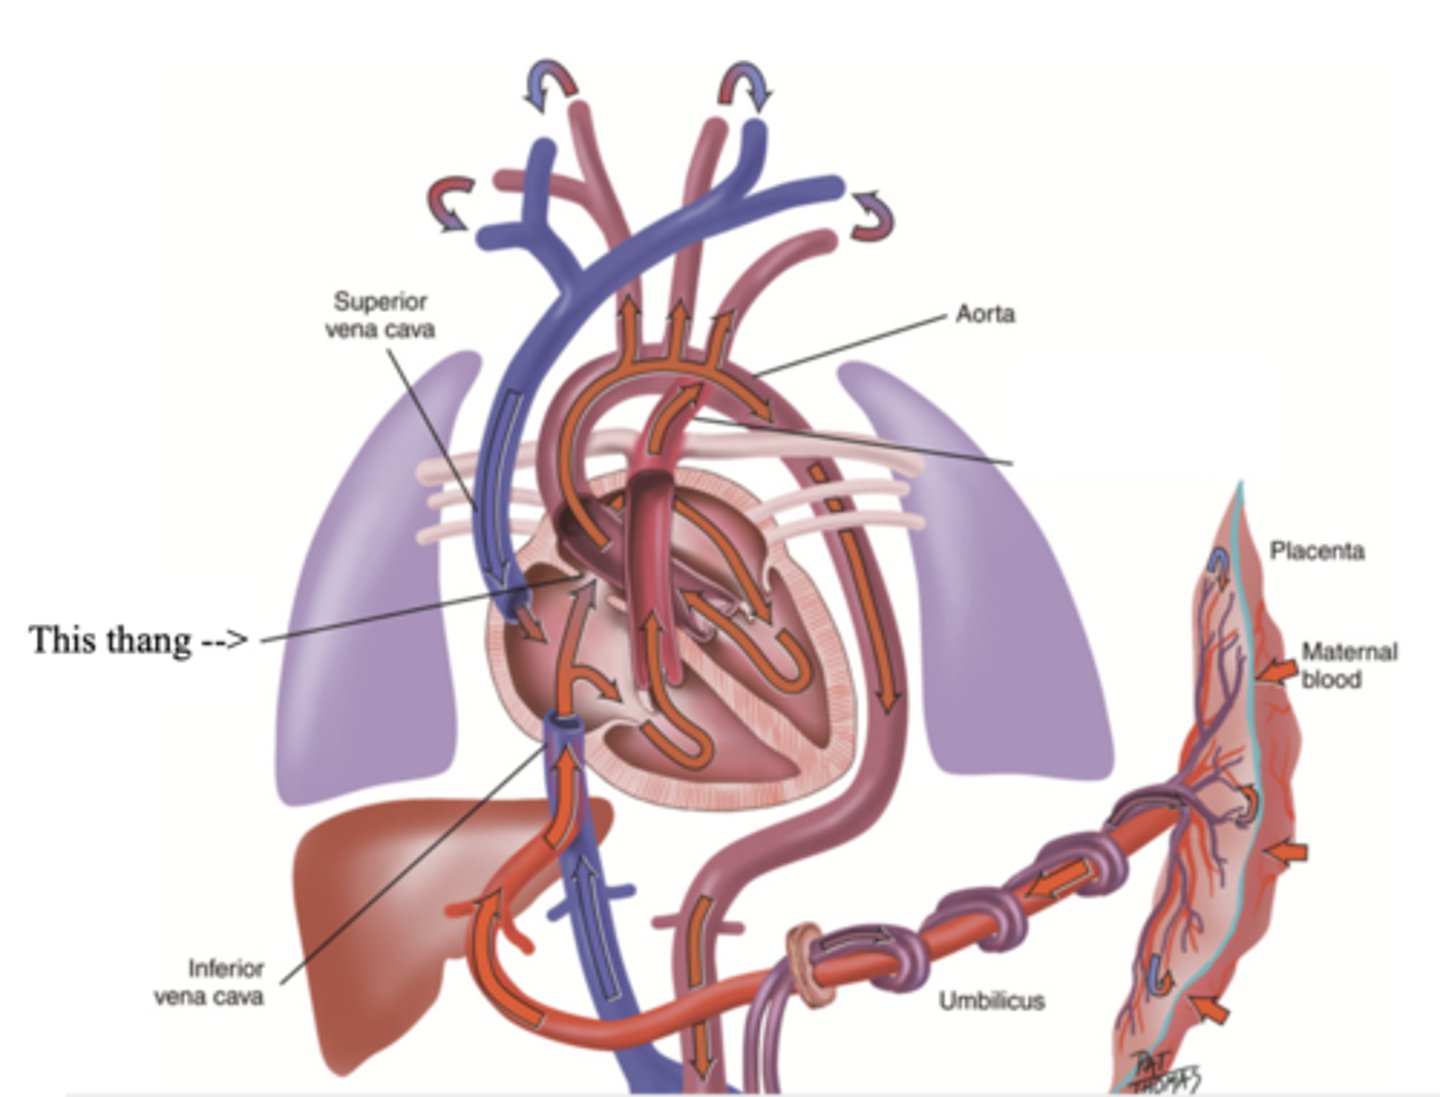

Foramen Ovale

A hole that connects the two atria in the fetal heart

Ductus Arteriosus

A blood vessel in a fetus that bypasses pulmonary circulation by connecting the pulmonary artery directly to the ascending aorta

Developmental Heart Considerations for Pregnant Women

- Increase in blood volume

- Increase in stroke volume

- Increase in cardiac output